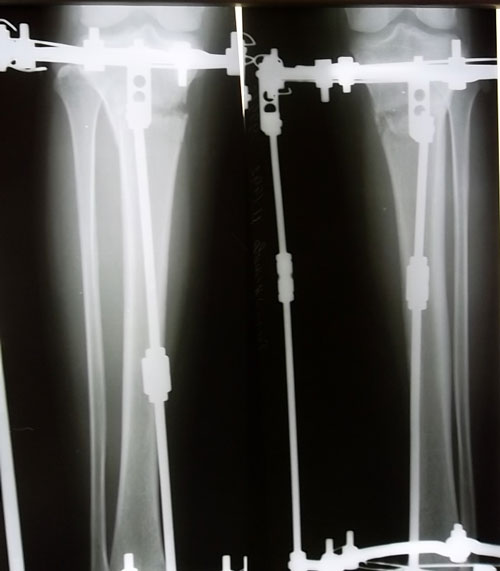

Рентгеновские снимки в 2 месяца после операции.

По рентгеновским снимкам сращение идёт хорошо, но ещё немного походим. В 3 месяца можно приезжать на снятие аппаратов. Дату приезда согласуйте со мной!